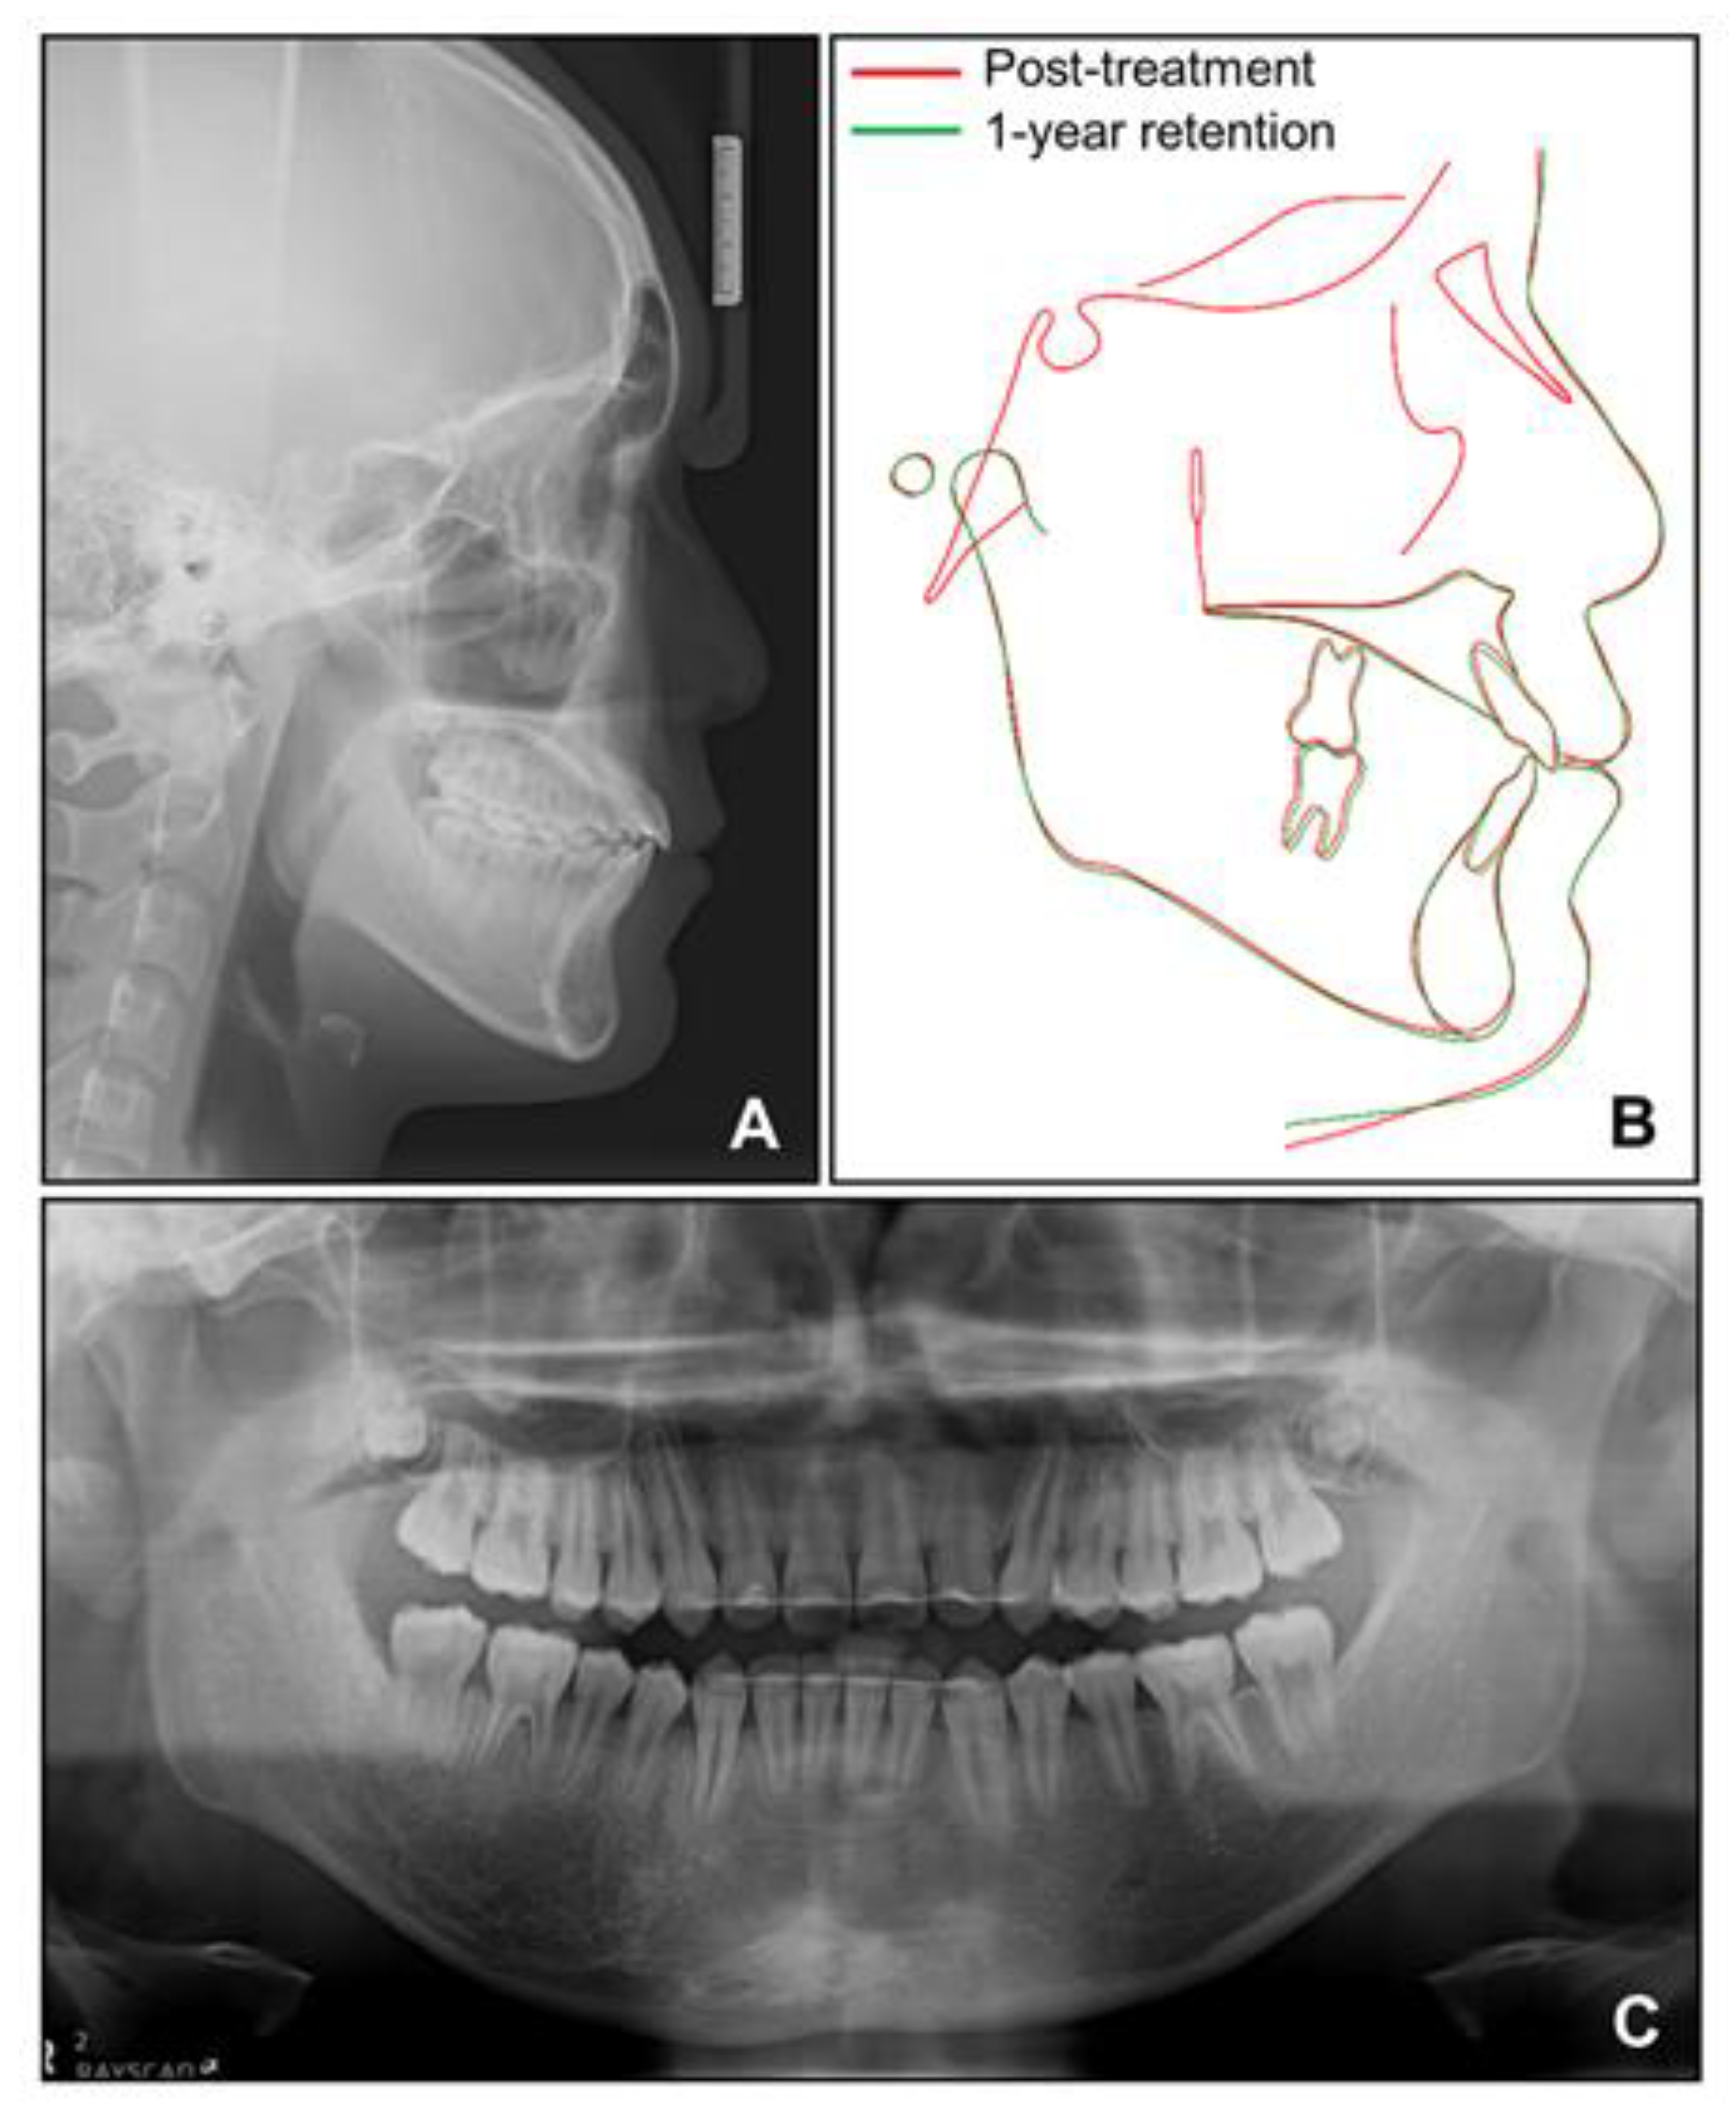

Cephalometric analysis showed that a skeletal Class I relationship was well-maintained after the phase 1 treatment, with an ANB of 2.5°. Both previously lingually inclined maxillary and mandibular incisors were improved to the normal range. The patient was satisfied with the results and remained stable for 1 year after debonding. While a slight relapse pattern of open bite was observed in the left anterior region, no remarkable increase in the right mandibular right hypertrophic region was observed (Figure 13 and Figure 14).

Figure 14. Radiographs for 1-year retention. (A) Lateral cephalogram; (B) Superimposition between post-treatment and 1-year retention; (C) Panoramic radiograph.